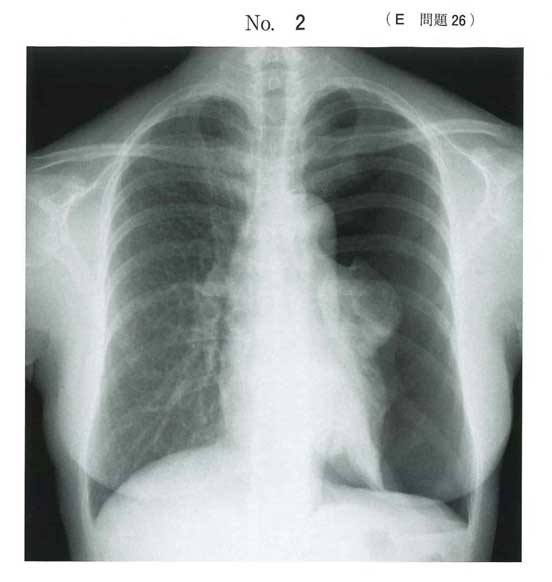

「血圧低下+頸静脈怒張+片側呼吸音消失」

→ 緊張性気胸

→ まず脱気